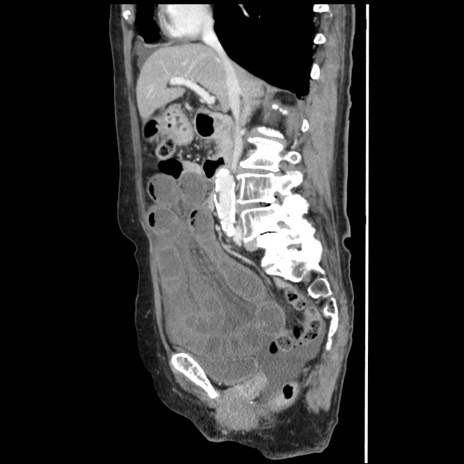

症例1(矢状断像)

【症例】80歳代女性

【主訴】腹痛

【現病歴】8時間前から腹痛あり来院。

【既往歴】糖尿病、脂質異常症、子宮体癌にて子宮全摘術

【身体所見】意識清明・会話良好だが腹痛で苦悶様、全腹部にわたって反跳痛と圧痛あり

【データ】WBC 13600、CRP 0.14、LDH 224、CK 90